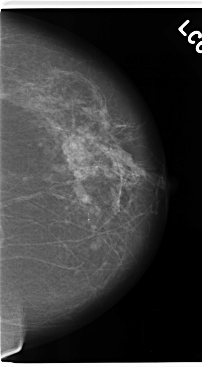

ics_version 1.0 filename C-0172-1 DATE_OF_STUDY 8 5 1996 PATIENT_AGE 70 FILM FILM_TYPE REGULAR DENSITY 2 DATE_DIGITIZED 12 3 1998 DIGITIZER LUMISYS LASER SEQUENCE LEFT_CC LINES 4760 PIXELS_PER_LINE 2616 BITS_PER_PIXEL 12 RESOLUTION 50 NON_OVERLAY LEFT_MLO LINES 4720 PIXELS_PER_LINE 2816 BITS_PER_PIXEL 12 RESOLUTION 50 NON_OVERLAY RIGHT_CC LINES 4696 PIXELS_PER_LINE 2680 BITS_PER_PIXEL 12 RESOLUTION 50 OVERLAY RIGHT_MLO LINES 4640 PIXELS_PER_LINE 2976 BITS_PER_PIXEL 12 RESOLUTION 50 OVERLAY |